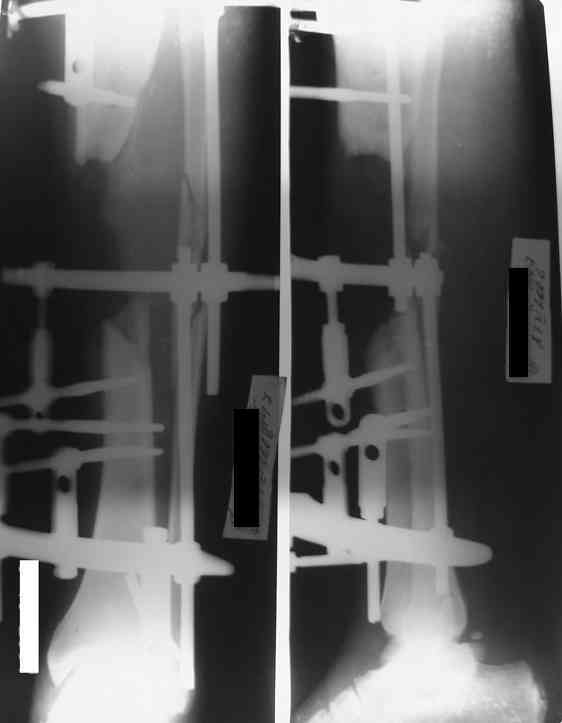

Владимир, свободная костная пластика на фоне свища вряд ли оправдана. Почему не рассматриваете вариант транспорта кости по Илизарову? Что собираетесь делать с латентной инфекцией? Одни антибиотики не помогут, необходима полноценная хирургическая обработка, Мы бы подумали о цементном спейсере с антибиотиками, бусах. После купирования инфекции переходить к замещению

дефекта: за счет удлинения концов б\б кости или тибиализации м\б. На начальном этапе фиксация только в аппарате, в последствие для удержания достигнутого можно перейти на фиксацию интрамедуллярным штифтом (см. вложенные файлы)

Как дополнение высылаю снимки и фото конечности, чтобы Вы могли оценить состояние м/т, и течение заболевания.